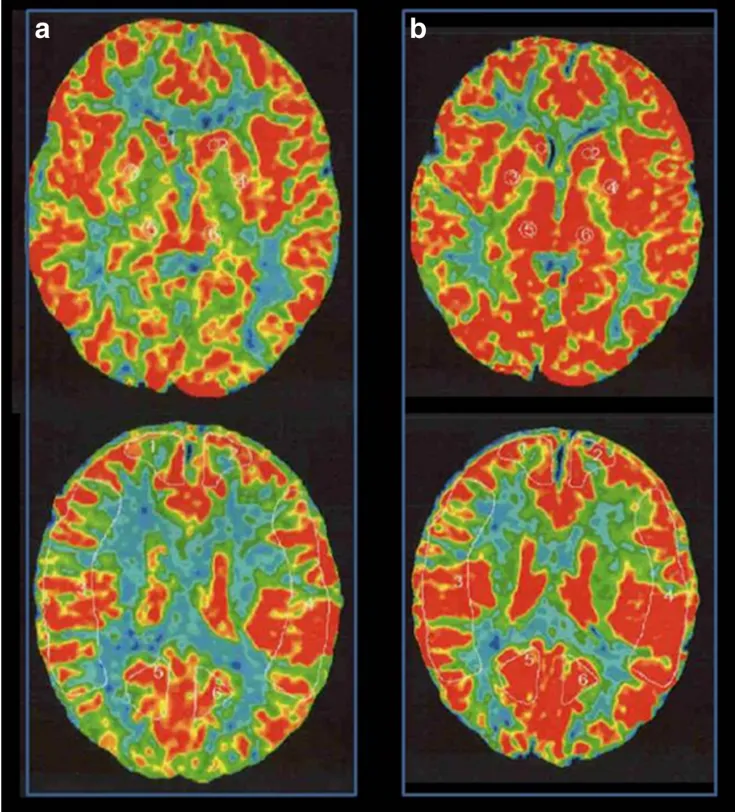

脑血管造影显示,小雨属于右侧单侧烟雾病,Suzuki分期为II期(或II–III期过渡)。令人惊讶的是,其脑血流(CBF)检查并未显示明显下降。

术前Xe-CT显示静息状态无偏侧(a),注射丹木斯(Diamox)后右侧MCA区域脑血管反应性为14.8%(b)。